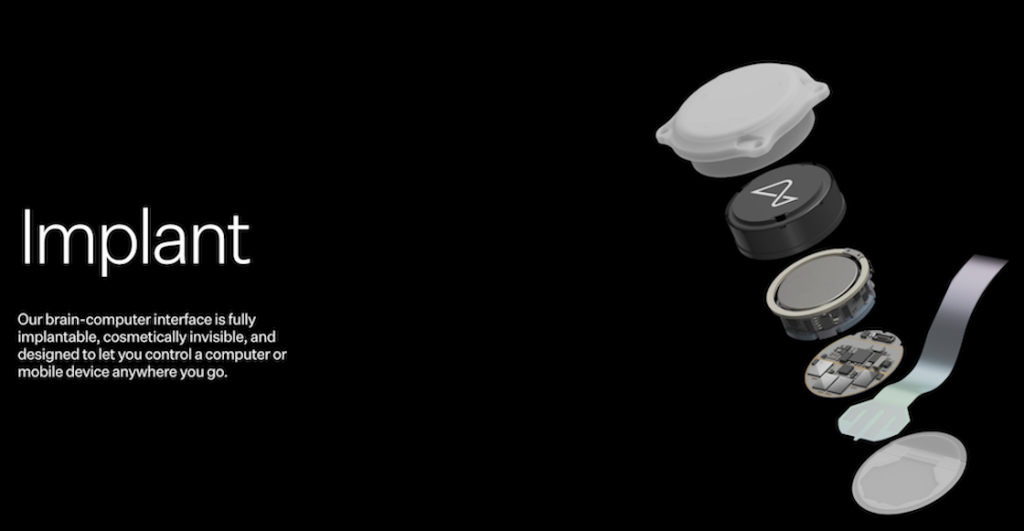

La razón por la que los primeros voluntarios humanos del chip cerebral de Neuralink tienen que tener una discapacidad motriz es que la empresa espera que su dispositivo pueda darles la posibilidad de controlar un cursor o un teclado “solo con sus pensamientos”.

En la primera van a probar los resultados del chip N1, su prometida interfaz controlada por impulsos cerebrales. Esperan que sea completamente invisible y que los 1,024 electrodos, conectados en 64 hileras funcionen a la perfección.

En la segunda van a estudiar al robot R1, que es el dispositivo que implanta el chip. En la tercera revisarán las funciones de la N1 User App, un software que transforma las señales cerebrales o los impulsos eléctricos en órdenes computacionales como escribir un mensaje o apuntar un cursor. Durante este estudio se probarán sus funciones y por supuesto, su seguridad.